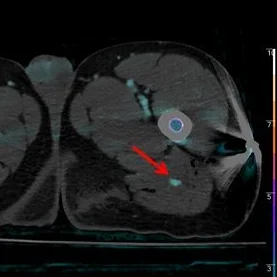

Iodine overlay shows ative extravasation very well (red arrow).